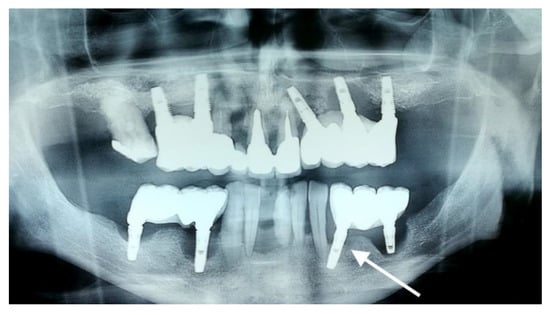

The first implant (Sample 1) was obtained from a 64-year-old male patient. The rejected implant was identified on the orthopantomography (OPG) in position 3.5 (Figure 2, arrow). The implant was placed approximately five years ago and the prosthesis was a porcelain fused to metal (PFM) crown. At initial appointment, the patient complained of tenderness and bleeding on brushing at the implant sites. The cervical part of the implant was uncovered in the oral cavity. The clinical examination revealed implant mobility, gingival retraction, local inflammation, and poor oral hygiene. The patient interview uncovered he was a smoker of approximately 20 cigarettes per day and suffered from untreated arterial hypertension. The implant was removed and the site was allowed to heal for four months, then another implant was inserted at the same site.

Figure 2. OPG radiography revealing peri-implantitis in quadrants 1, 2, and 3. The implants inserted in positions 1.2, 1.4, 1.6, 2.2, 2.4, 2.6, 3.5, 3.6, and 3.7 show generalized vertical and horizontal bone loss. The investigated implant is marked with an arrow.